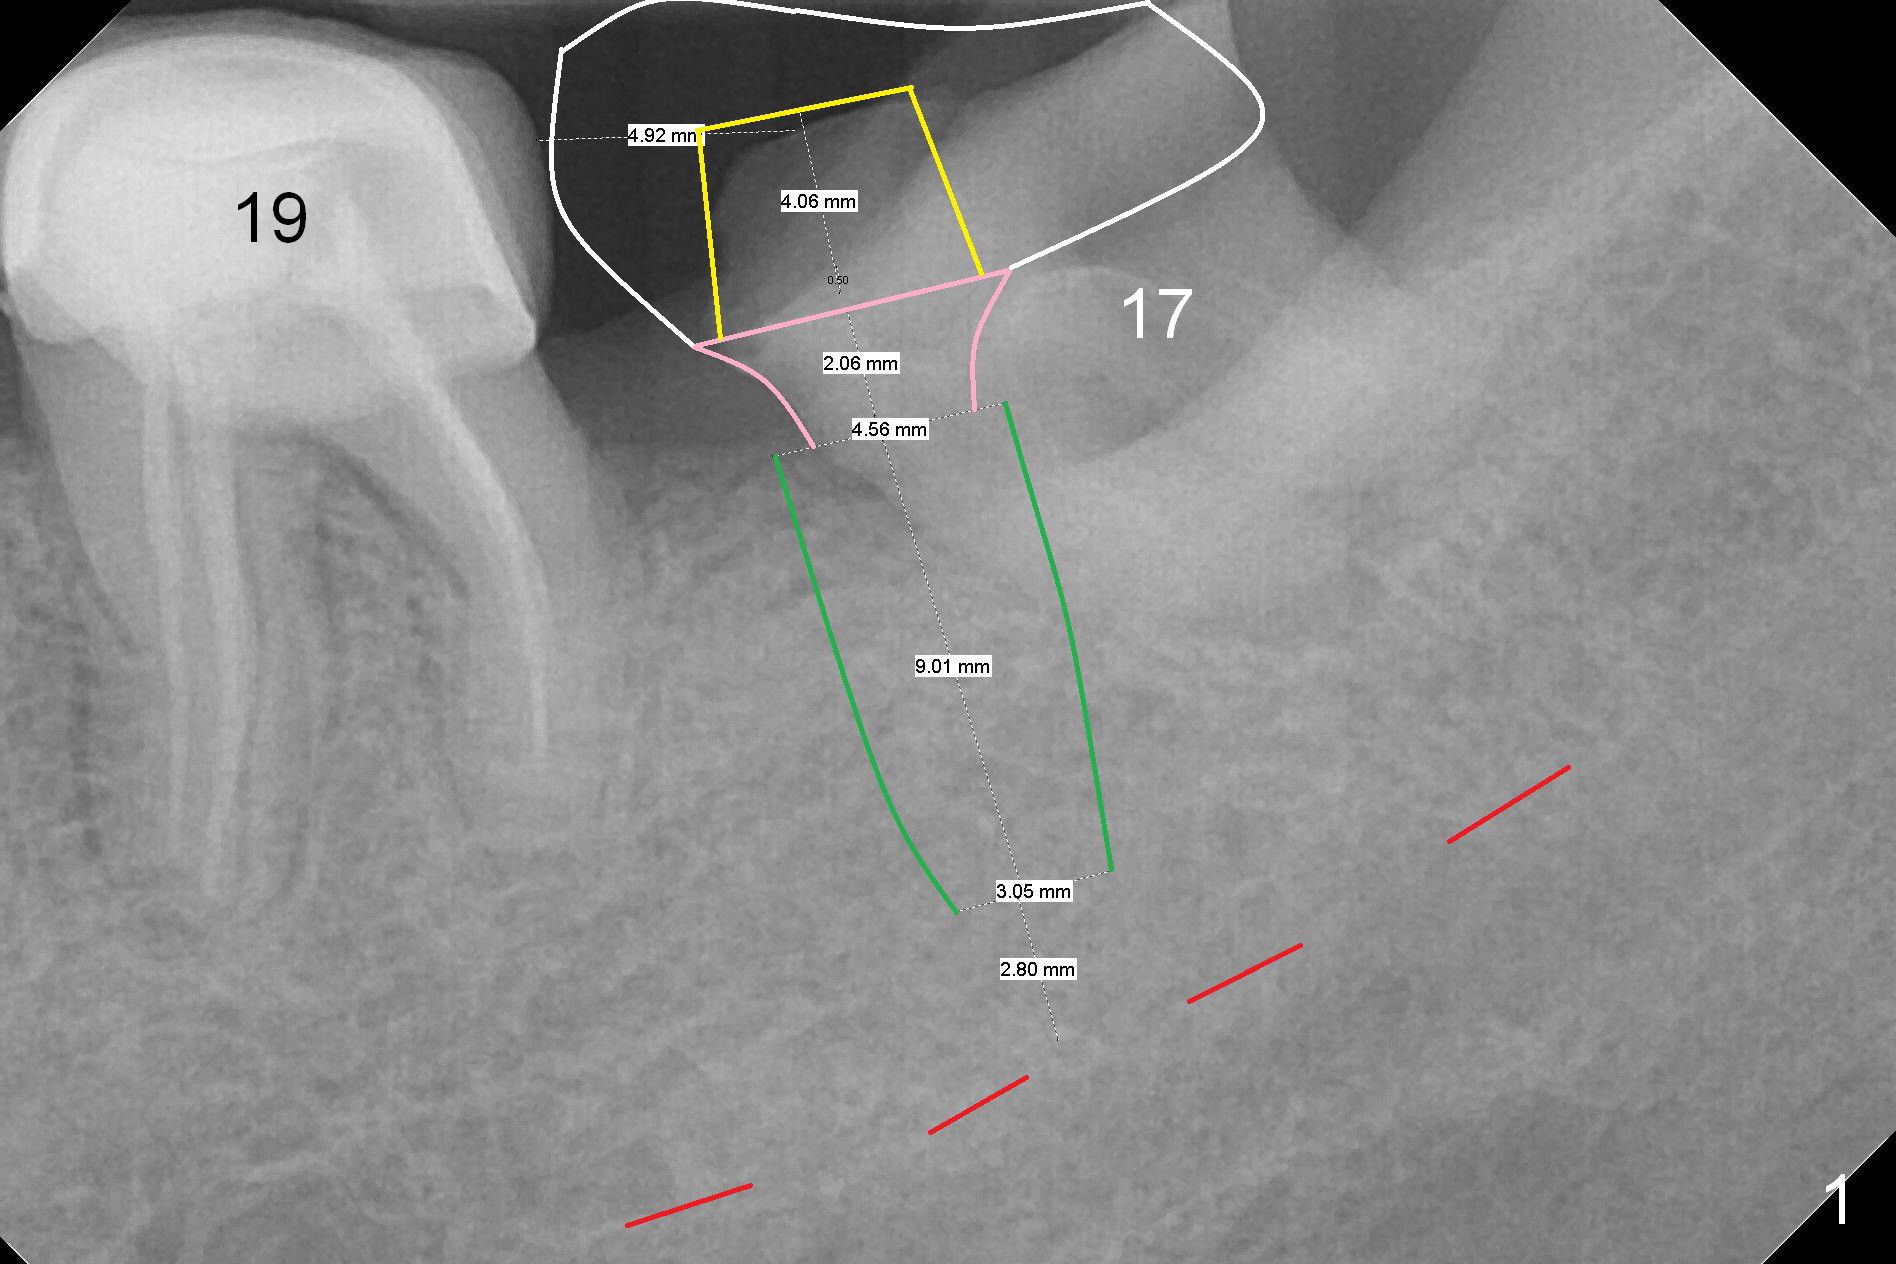

Place 2nd Molar Implant in 3rd Molar Socket

A 47-year-old woman is going to have an implant for #18 (Fig.1). Since the tooth #17 has migrated mesially so much that the implant will be placed in the mesial socket of the tooth #17 (green area) immediately after extraction (no antibiotic). After immediate placement of an abutment (yellow and pink), an immediate provisional will cover the sockets of #17 (white).